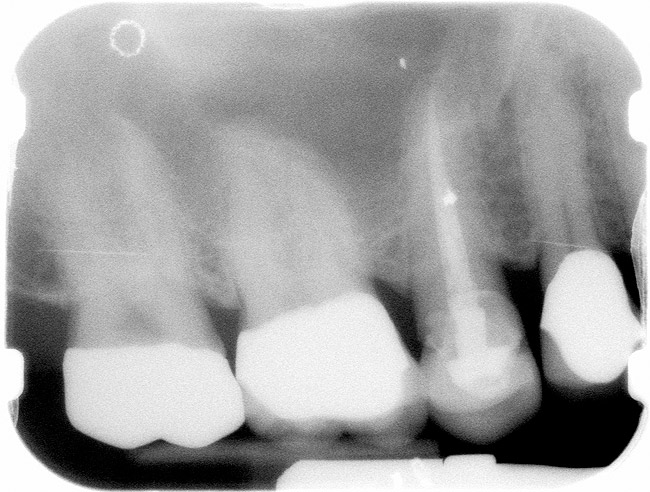

Figure 1  X-ray of an endodontically treated second bicuspid restored with a fiber post, core, and all-porcelain crown.

Figure 1